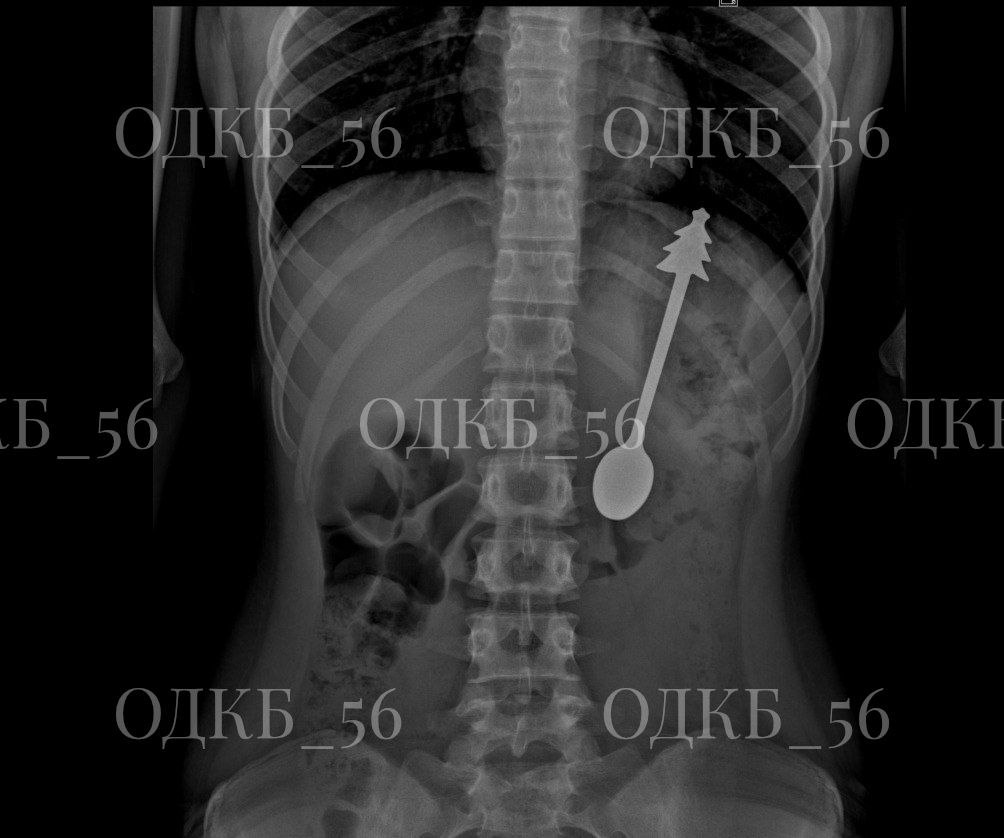

Маленького пациента доставили в больницу на скорой помощи. Диагностика показала, что ребенок проглотил ложку длиной 14 сантиметров.

Ребенка госпитализировали в отделение хирургии. Врачи приняли решение удалить инородный предмет эндоскопически. Вмешательство провела команда специалистов в условиях общего обезболивания в экстренном порядке. Металлическую ложку успешно достали из желудка.

Фото: ОДКБ